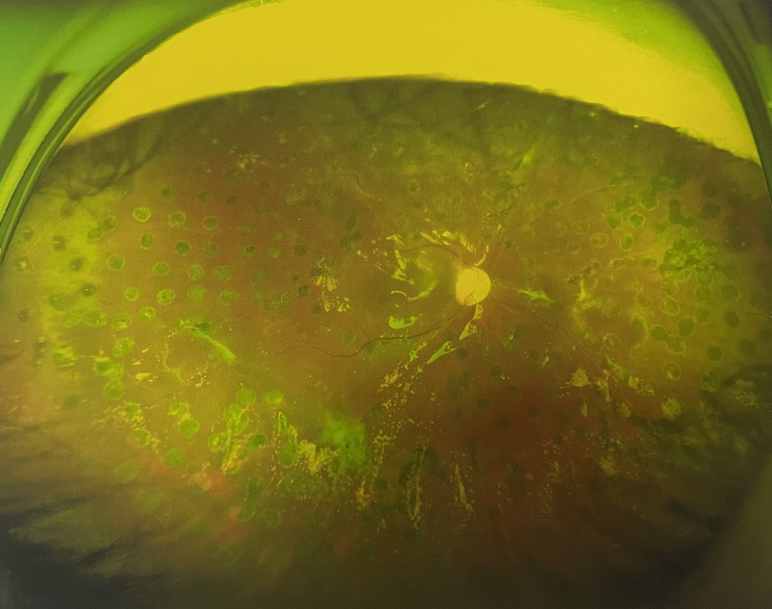

張小虎醫(yī)生為王女士進(jìn)行右眼玻璃體腔注藥術(shù),3天后進(jìn)行右眼23G玻璃體切割術(shù)后視力有所提升。

4個(gè)月后王女士來(lái)院取硅油,取油后視力恢復(fù)到0.6。“當(dāng)時(shí)來(lái)的時(shí)候真的只能看到模糊的影子,特別害怕覺得完了,想說(shuō)眼睛估計(jì)要瞎了,沒想到手術(shù)后視力竟然提升了,現(xiàn)在也看得比較清楚了。”王女士說(shuō)到。

張小虎醫(yī)生表示,糖網(wǎng)病進(jìn)展到嚴(yán)重增殖期帶來(lái)的視力損傷往往是極其嚴(yán)重的,目前王女士右眼從術(shù)前0.02恢復(fù)到術(shù)后0.6,已屬十分難得。

右眼術(shù)后